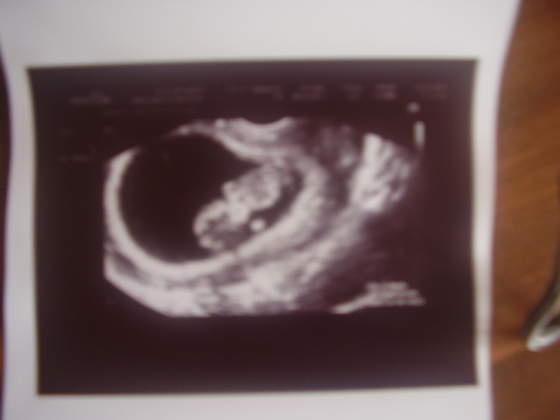

Podobne "ujęcie" miała nasza dziewuszka w 10 tyg. Słodziak! Te łapki kropeczki